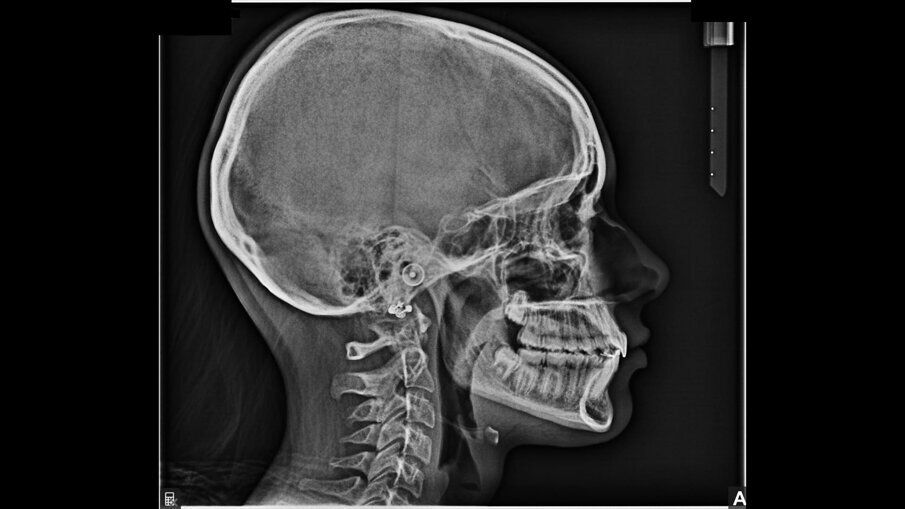

All’esame obiettivo intraorale si riscontra sul piano frontale un severo morso profondo con precontatto traumatico degli incisivi superiori contro la papilla retroincisiva e le rughe palatine anteriori durante la massima intercuspidazione, con overbite di 10 mm (Fig. 5). Dalle foto laterali si evidenzia una malocclusione di Classe II divisione 2 con scissor bite dell’elemento 1.5 (Figg. 6, 7), mentre dalle foto occlusali si rileva un grave affollamento con contrazione di entrambe le arcate maggiore nella zona premolare (Figg. 8, 9). L’analisi di Bolton mostra un eccesso superiore 3-3 di 2,34 mm (73,6%) e 6-6 di 2,76 mm (88,8%). L’analisi cefalometrica evidenzia una Classe II scheletrica, modello facciale normodivergente, angolo interincisale aumentato, incisivi superiori e inferiori retroinclinati (Fig. 10). La radiografia panoramica mostra la presenza dei germi dei terzi molari, assenza di parallelismo tra le radici dei premolari inferiori (Fig. 11) e una sovraeruzione degli incisivi inferiori che crea un doppio piano tra gli incisivi e i molari, segno di una curva di Spee molto profonda.

Fig. 10_Teleradiografia pre-trattamento.